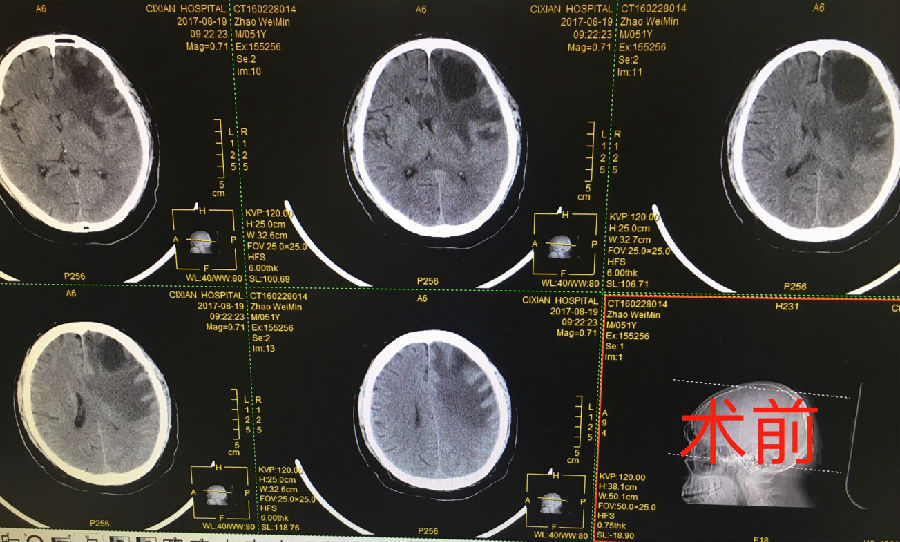

近日,在神經(jīng)外一科李春輝主任的帶領(lǐng)下,我院完成首例腦轉(zhuǎn)移瘤切除的開(kāi)顱手術(shù),術(shù)后患者癥狀緩解,生命得以延續(xù)。